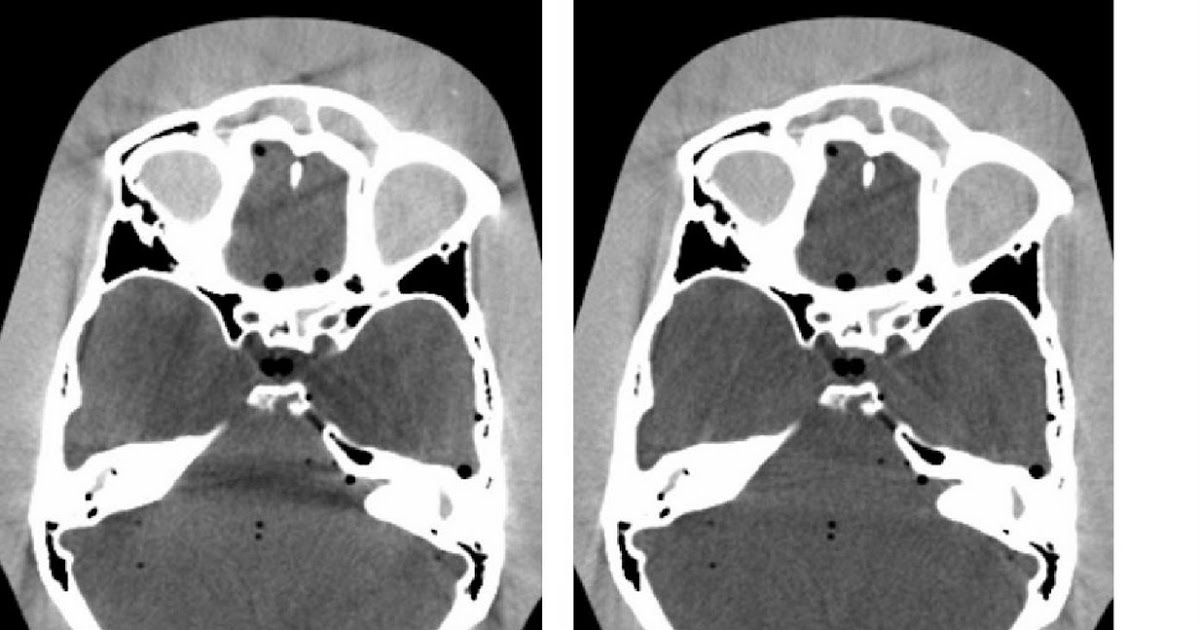

Ct Tube Arcing Artifact . One or more concentric rings in image. the described tube arcing artifact seen in ct images was caused by a fault with the. Ct 37 artifact from tube arcing (frame from animation in presentation)

One or more concentric rings in image. the described tube arcing artifact seen in ct images was caused by a fault with the. Ct 37 artifact from tube arcing (frame from animation in presentation)

Ct Tube Arcing Artifact One or more concentric rings in image. One or more concentric rings in image. Ct 37 artifact from tube arcing (frame from animation in presentation) the described tube arcing artifact seen in ct images was caused by a fault with the.